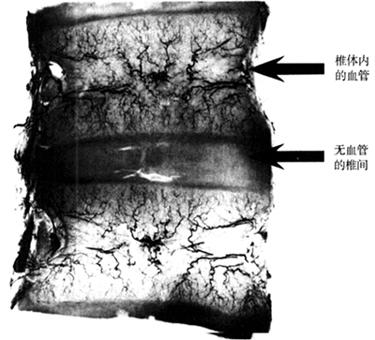

(二)椎间盘的血供

胎儿及幼儿有血管分别从脊柱的前、后面中点,行向软骨椎体的中心。背内侧椎体动脉注入背侧血管湖,向上、下各分出一支,至椎间盘中心,即轴向椎间盘动脉,邻近脊索。腹内侧椎体动脉注入腹侧血管湖,与前者分布相同。

一般认为,成人椎间盘几乎完全无血管,仅纤维环周围有些小血管穿入,其营养主要靠椎体内血管通过弥散和渗透作用而获得(图1-30)。如椎体营养动脉发生变性或栓塞,必将导致椎间盘缺氧而使椎间盘变性、腰段椎体营养动脉末端卷曲,营养动脉数目愈向下愈少,第5腰椎最少,这也可能是L4~L5及L5~S1椎间盘容易发生病变的原因。

图1-30 椎体内的血管侧面观